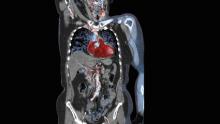

Physicians have used radiation in medicine for more than a century. The use of radiation in diagnostic imaging, including computed tomography (CT), fluoroscopy, angiography, mammography, computed radiography (CR) and digital radiography (DR), as well as in nuclear medicine, has aided greatly in the diagnosis and treatment of cancer and other diseases.